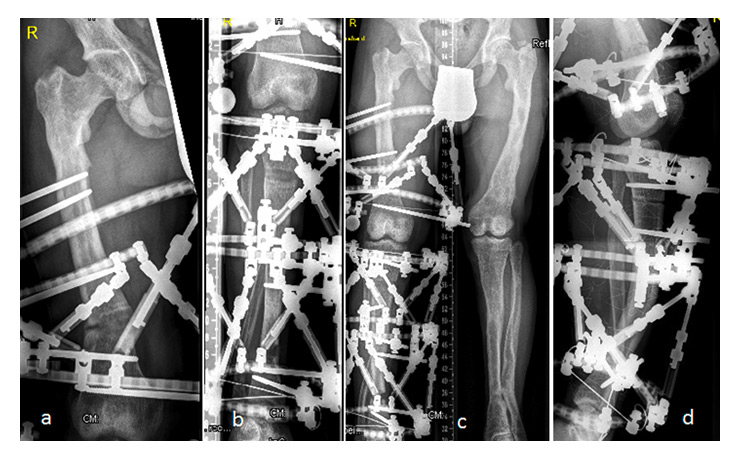

Figure 2

After proximal and distal femoral osteotomy, or a proximal tibial osteotomy of the lower limbs (in different patients), a Taylor spatial frame was applied.

Regardless of the type of fixation used, we carried out careful preoperative planning and assessment of the surgical treatment to realign the deformities. In our current patients, multiple osteotomies in three planes were required in both the tibiae and the femora, as well as limb-length equalisation; the aim was to correct satisfactorily the mechanical axis deviation of the limb. After a proximal and distal femoral osteotomy, or a proximal tibial osteotomy of the lower limbs (in different patients), a Taylor spatial frame was applied (fig. 2). After femoral or proximal tibial osteotomy along the lower limbs (in different patients), the severe varus deformity was corrected by gradual distraction using a Taylor spatial frame. External fixation allowed fine-tuning of the alignment postoperatively (fig. 3). After full correction and acceptable bony consolidation, intramedullary fixation by means of locked nails was inserted along the right femur, and the patients were able to stand. Alignment and orientation are best judged using standing long anteroposterior view radiographs of the entire lower extremity.